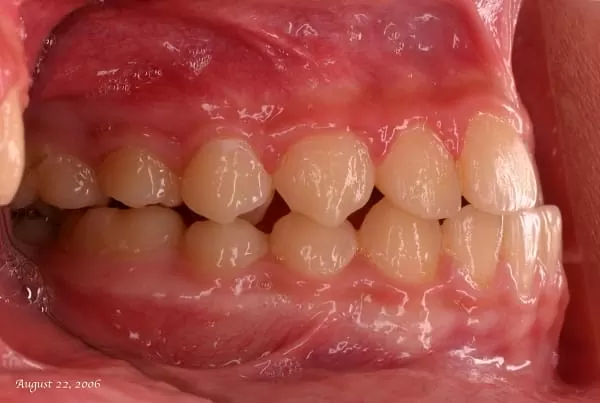

矯正前

- 當兒童過了學齡期,來到青少年時期,青春期是生長發育快速的時期,青少年的骨骼在此時期正在快速地增長,「身體長骨」的生長與「顎骨」的發育是密切相關的,尤其大部份的女生生長發育期在經期後約2~3年「身體長骨」的發育就已成形,男生在此時期的發育則較快。

- 此時期家長們若發現正值青春期的孩子有牙齒生長錯亂或發展緩慢的異常狀況,可適時地透過齒顎矯正去引導它,來幫助及促進牙齒的生長發展。